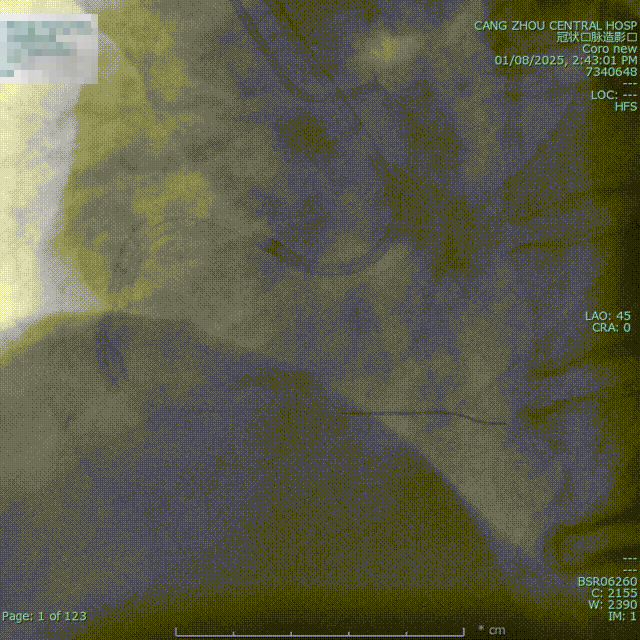

造影显示

1.LM未见明显狭窄;

2.LAD 支架术后,原支架通畅;

3.LCX支架术后,原支架通畅;

4.RCA:支架术后,支架内完全闭塞;

5.RCA优势型。

结论:三支病变,RCA支架内闭塞。

综合考虑后决定对右冠进行介入治疗。